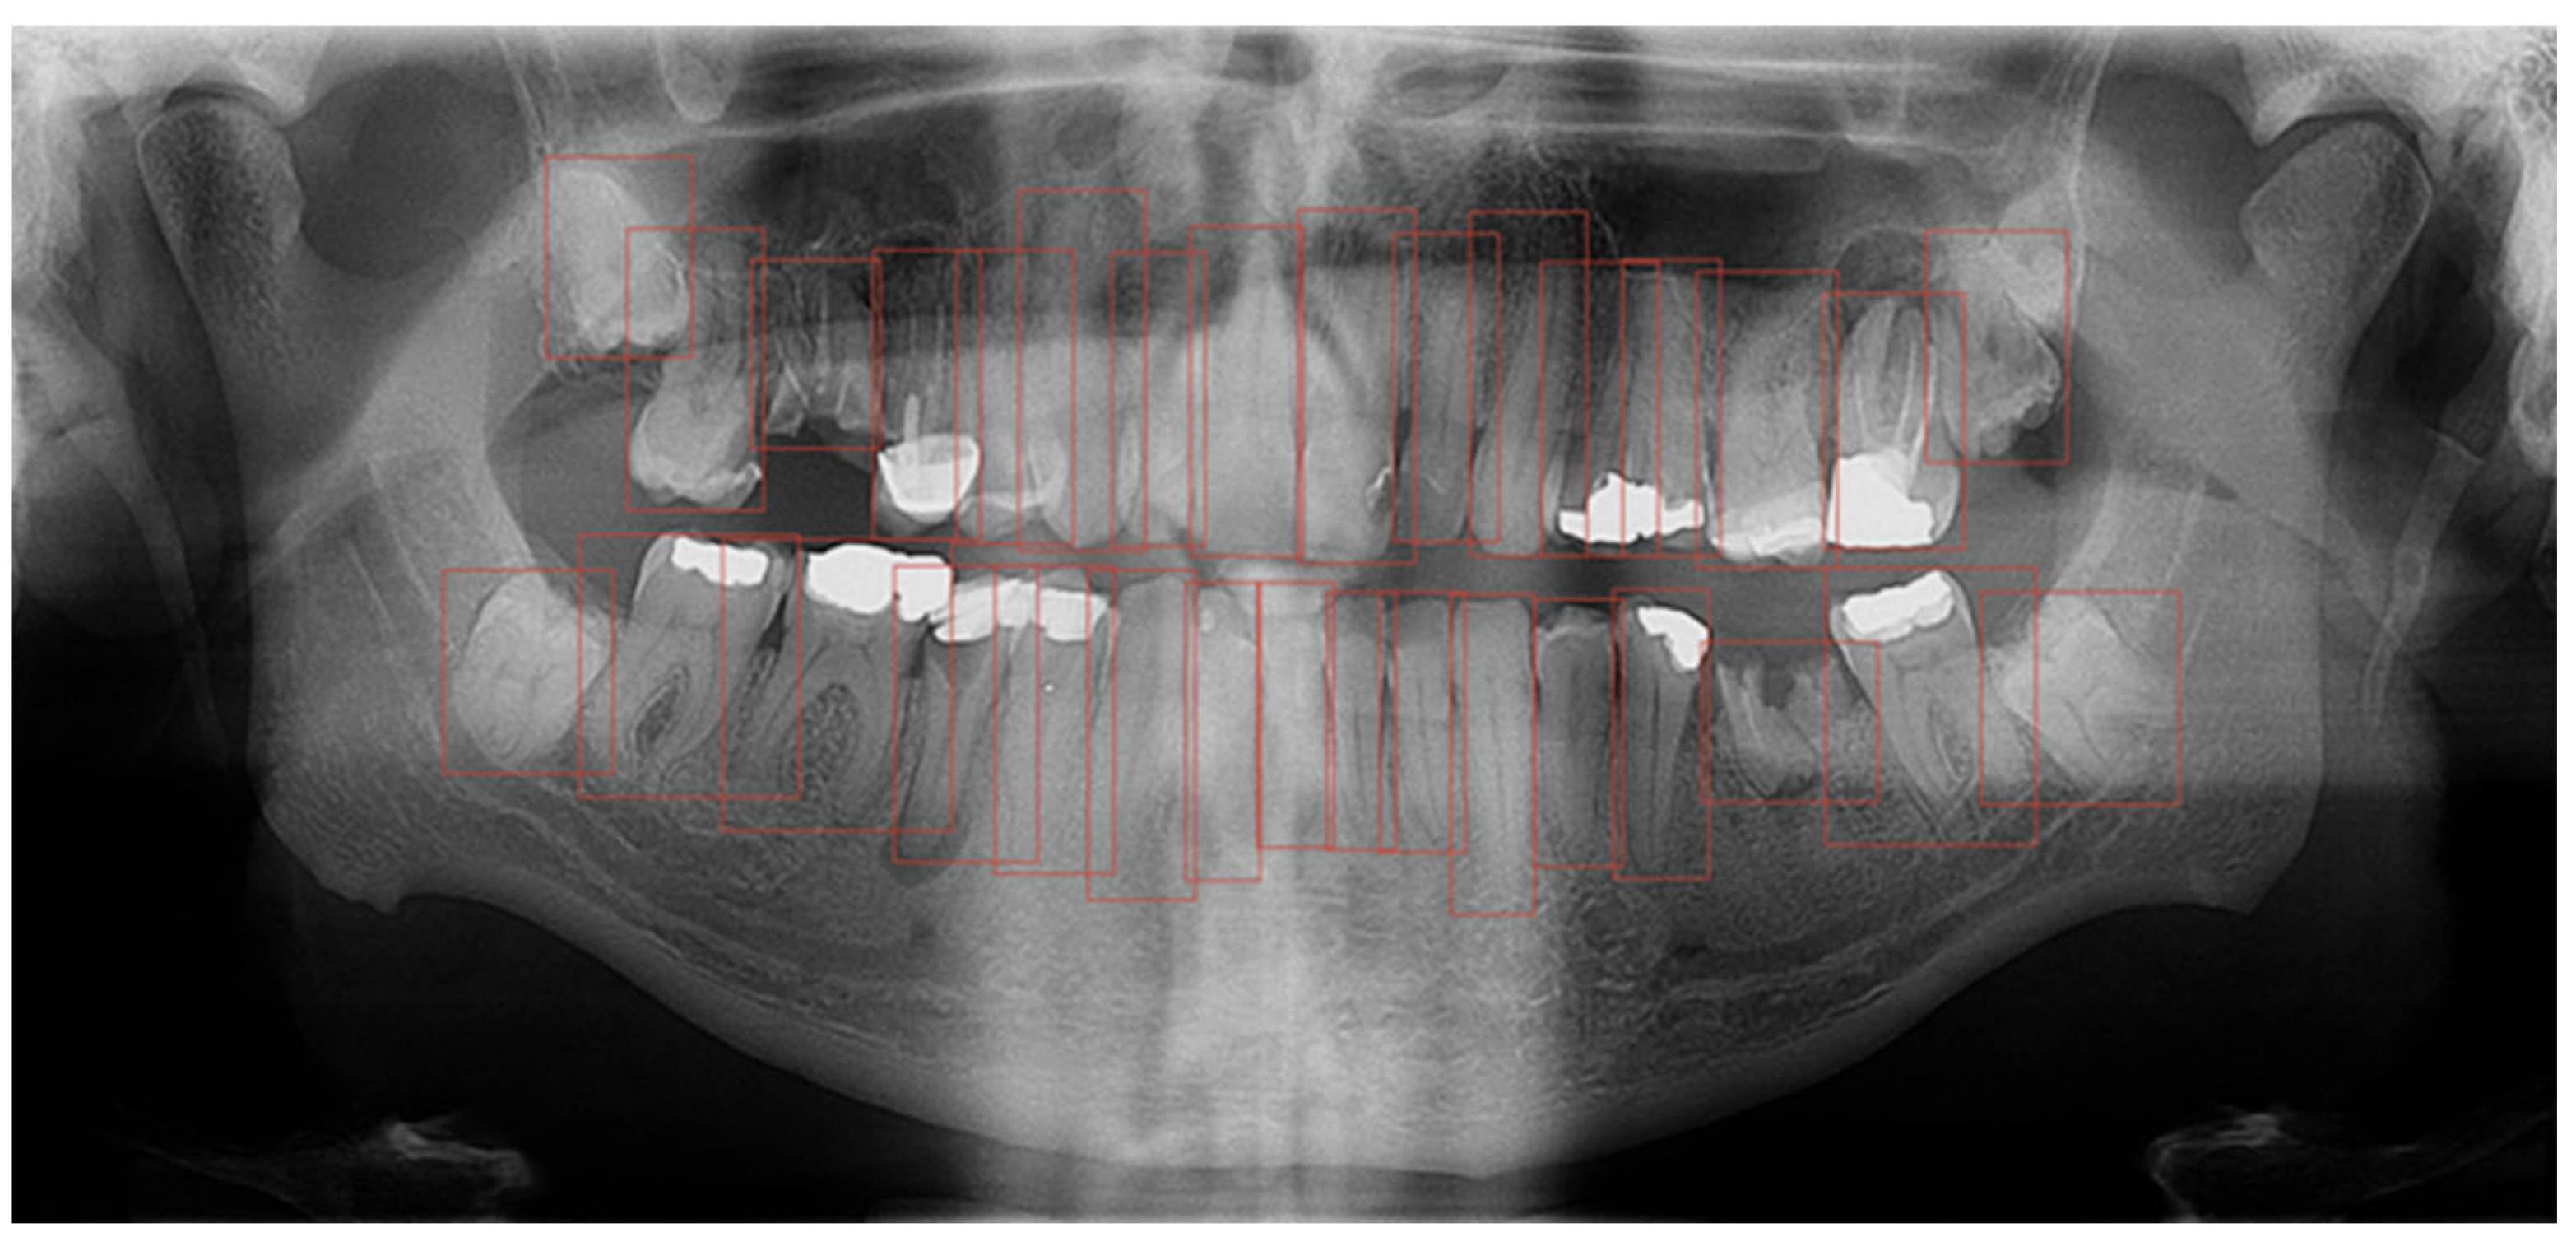

The computer program GIMP 2.10.22 was used to process the OPGs. GIMP is a powerful, free, and open-source image editor. The tool’s editing capabilities provided the annotators with a robust toolbox to adjust image parameters, helping them better discern the boundaries of the target regions. Importantly, the original OPGs were not modified during this process; everything except the annotated masks was discarded. Additionally, GIMP’s open format facilitated easy handling of per-pixel annotation data. Regarding annotation speed and validation, marking an entire tooth took about 10 min, while segmentation time depends on the number of interventions the tooth has undergone. For validation, we conducted multiple rounds of annotation-review iterations. Annotations were saved as XML files in the PASCAL VOC format for further use in neural networks. Every annotation step was conducted manually by a human expert; no annotations were automatically generated. Within the program, each tooth was outlined, covering the entire range of the tooth, including the crown and root (Figure 1). Teeth were labelled using the dual or binary system (FDI).

As a second layer, after outlining the teeth, each filling, crown, bridge, implant, endodontic filling, and tooth build-up was marked (Figure 2).

Figure 1. Segmentation of teeth on OPG in the GIMP program.

Figure 2. Segmentation of dental interventions on OPG in the GIMP program.